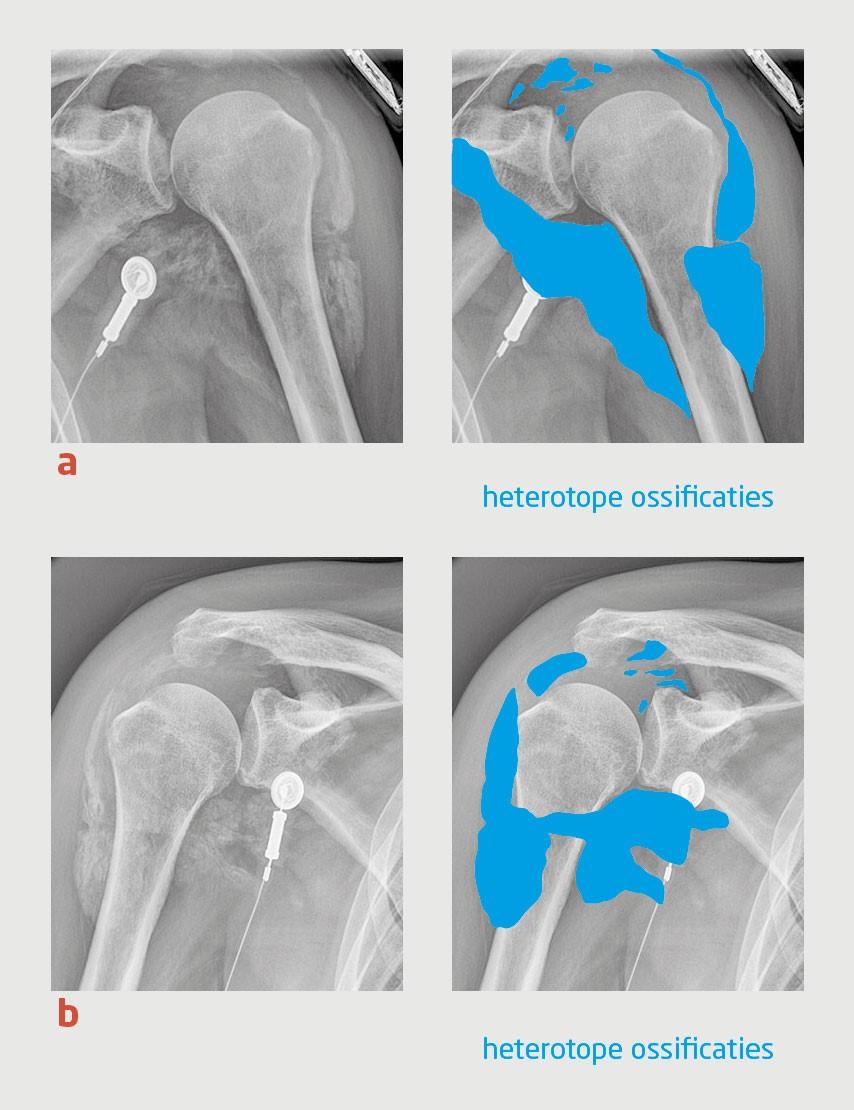

Figuur 2

Heterotope ossificaties rondom de glenohumerale gewrichten van patiënt B.

Figuur 2 | Heterotope ossificaties rondom de glenohumerale gewrichten van patiënt B.

Röntgenfoto’s van (a) de linker en (b) de rechter schouder van patiënt B. Er zijn uitgebreide heterotope ossificaties rondom de beide glenohumerale gewrichten zichtbaar.